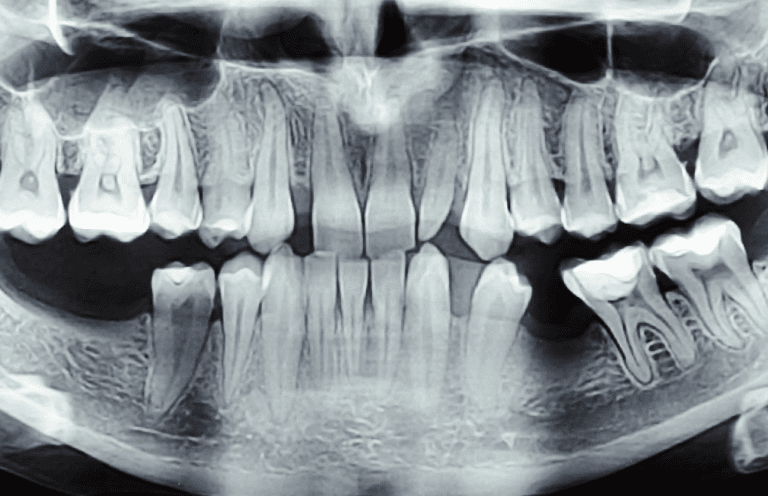

تحليل الأسنان

تحليل الأسنان للتعرف على الأشخاص (Forensic Odontology) هو مجال في الطب الشرعي يستخدم الأسنان لتحديد هوية الأفراد. تعتمد هذه العملية على أن الأسنان فريدة لكل شخص ومقاومة للغاية للتحلل والتلف، مما يجعلها مصدرًا موثوقًا للمعلومات حتى بعد الكوارث. تتم مقارنة السجلات السنية المتاحة للتعرف على الرفات المجهولة أو ضحايا الحوادث.